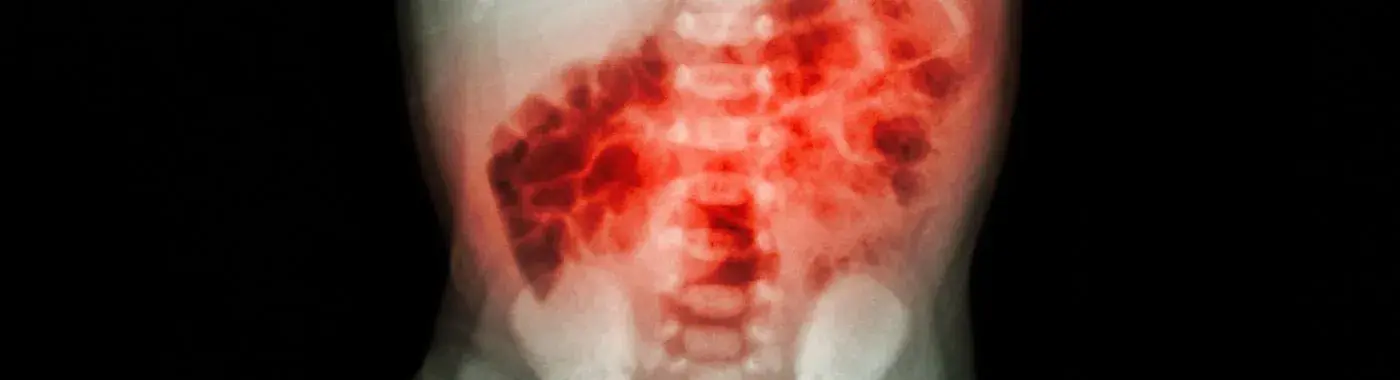

Necrotizing Enterocolitis (NEC) is a severe gastrointestinal condition primarily affecting premature infants. It is characterized by inflammation and necrosis (tissue death) of the intestines, which can lead to serious complications and even death if not promptly treated. Understanding NEC is crucial for parents, caregivers, and healthcare professionals, as early recognition and intervention can significantly improve outcomes. This article aims to provide a comprehensive overview of NEC, including its definition, causes, symptoms, diagnosis, treatment options, complications, prevention strategies, and prognosis.

Necrotizing Enterocolitis is a serious intestinal disease that primarily affects premature infants, particularly those born before 32 weeks of gestation. The condition occurs when the intestinal tissue becomes inflamed and begins to die, leading to potential perforation of the intestine and the risk of infection spreading throughout the body. NEC is considered a medical emergency, and its management requires immediate attention from healthcare professionals.

• Abdominal X-rays: These can reveal signs of intestinal obstruction, perforation, or air in the abdominal cavity.

• Ultrasound: This imaging technique can help visualize the intestines and assess for abnormalities.